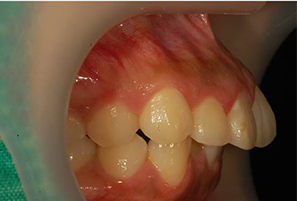

실제 치료 사례

데이몬 교정으로 완성된 아름다운 변화를 확인하세요

비발치 데이몬 교정

치아를 뽑지 않고도 완벽한 치열 개선